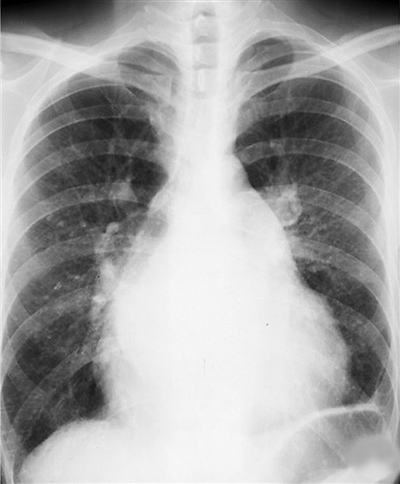

刚刚入秋,“秋老虎”依然炙热灼人。炎炎烈日里,农民工刘克喜却每天都紧紧裹着身上厚重的毛衣。这半年来,肺炎和感冒如同老朋友似的“粘”上了他,而这种“交往”付出的代价是,他眼睁睁的看着健康如同空气般从体内一点点被抽走。矽肺病二期——在这个沉重的阴影下,他步履蹒跚,40步楼梯台阶整整爬了半个小时有余。

2008年,由于长期在粉尘环境中作业,刘克喜终于发病,他感到头晕眼花,胸闷。于是前往黔东南州人民医院检查,医生检查后告诉他很可能得了矽肺病。

2008年至2009年间,恒盛公司先后给职工开具了31份职业危害接触史证明,经贵州省疾控中心进一步诊断,这些工人中姜仁生、刘克喜等5名工人被确诊为矽肺病,另有部分职工被要求进行半年或一年医学观察。面对这些危险的端倪,恒盛公司依然视而不见。

终于,矽肺病的消息引起了越来越多职工的恐慌。今年3月,一些患病的职工将恒盛公司可能上千工人患职业病这一情况在百度贴吧、天涯社区等网站上发布,引起了中央领导高度重视,国家有关部门和贵州省有关部门分别组成督查组和调查组进驻公司,恒盛公司大量工人患矽肺病的黑幕才最终被揭开,企业首次被责令停产。今年4月,在上级部门的督促下,恒盛公司才对公司目前在岗在册和部分已离厂的工人总共1337人进行了职业健康检查。

截至7月2日,恒盛公司先后共有1343名职工进行职业健康检查和职业病诊断,最终确诊矽肺患者200例。

8月6日,贵州省召开全省安全生产通气会,会上宣布了对恒盛有限公司重大职业危害事故中相关责任人和单位处理意见。调查认为,恒盛公司这起职业危害事故是一起群发性、社会影响较大的责任事故。这起事故发生的主要原因,是工业硅冶炼过程产生的烟尘中游离二氧化硅含量较高,这些物质进入空气中成为可吸入颗粒物能直接进入人体肺部,长期吸入导致矽肺病。事故的发生与公司厂区布置不合理,生产设备较简陋,企业对职业卫生工作不重视,施秉县有关部门监管不力,把关不严等有直接关系。